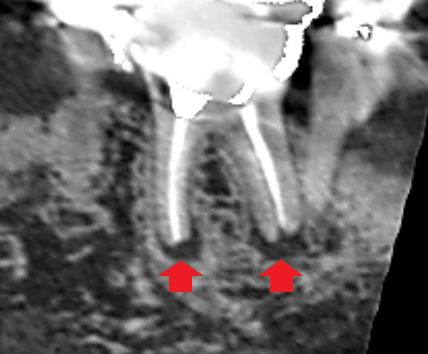

下顎第一大臼歯の初診時のCT画像です。

赤い矢印の先に膿の影がみられます。二本の根の両方に膿がみられ、両方の膿を改善しなければいけません。